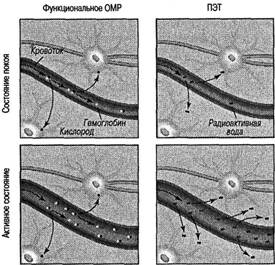

Начиная с 1-го и вплоть до 6-го издания «Когнитивной психологии» общая структура статей мало изменилась, но значительно изменилось их содержание. В первых изданиях мы лишь вскользь упоминали о теме, которая сейчас называется нейропознанием (термин начал широко применяться только в начале 1980-х годов). Сейчас же важная роль нейропознания во всех сферах когнитивной психологии (так же, как и в остальных сферах) очевидна, и дошло до того, что этот раздел когнитивной науки начал вытеснять из учебников другие, более традиционные области. Значительные успехи в нейропознании (не только в методах, но и в способах получения данных и их интерпретации) в полной мерой отражены в настоящем издании учебника, хотя мы не забывали и о том, что когнитивная психология — это прежде всего наука о человеческом разуме: мыслях, умозаключениях, языке, памяти и роли сенсорных стимулов. Эти и другие проблемы познания иллюстрирует, объясняет и разъясняет нейропознание (более чем на одном уровне). Ввиду того что познание изучается психологией, я сохранил описание многих традиционных исследований, которые выдержали испытание временем и эмпирическую проверку, и добавил новые интересные материалы там, где это было необходимо. Всегда существует большой соблазн заменить старые концепции на новые, но эта замена оправданна лишь в тех случаях, когда более современные труды отображают новый аспект проблемы. В большинстве случаев старые исследования безупречно ясны, поэтому я оставил их без изменений. Кроме того, в связи с ростом интереса к психологическим аспектам когнитивной психологии в 6-м издании упомянуто множество нейрокогнитивных исследований, которые были включены в издание как новые доказательства когнитивных теорий. Создание первого варианта «Когнитивной психологии» более 20 лет тому назад было особенно сложной задачей, так как я не имел никакого примера для подражания, кроме изданной в 1967 году и ставшей классической книги Ульрика Найссера с таким же названием и сотни статей и материалов симпозиумов, в беспорядке разбросанных у меня в офисе и дома. Мне действительно повезло, когда в 1974 году я оказался на лекциях Эда Смита о познании в Стэнфордском университете (курс лекций, который позже читал я). Его организация материала отражена (хотя с некоторыми изменениями) в данной книге, так же как и во многих других учебниках о познании, и мне кажется, что Эд Смит, который был принят в Национальную академию наук, оказал большое влияние на то, как преподается когнитивная психология в Соединенных Штатах и во всем мире. Существует несколько дюжин учебников по когнитивной психологии и еще много других книг, в которых обсуждаются такие темы, как познание и юриспруденция, познание и психотерапия, познание и общество, познание и образование и т. д. Начиная с периода «когнитивной революции» сфера влияния занимающихся этой темой специалистов расширилась намного больше, чем я мог вообразить десятилетия назад. Однако, на мой взгляд, главные темы, сформировавшие эту дисциплину в то время, все еще актуальны, хотя за прошлые годы акцент сместился, — таков динамический характер жизнеспособных наук. Мне нравилось писать эту книгу, и, могу нескромно добавить, я даже с удовольствием перечитывал ее время от времени; теперь же, когда я ее заканчиваю, пришло время оглянуться назад с некоторой ностальгией. Когда я начал работать над 1-м изданием, у меня были лишь чистый лист линованной бумаги, обещавшая стать обшарпанной авторучка и сотни статей, журналов и книг по восприятию, памяти и мышлению в качестве материала для работы. Теперь я работаю, используя компьютер, который сам проверяет правописание и синтаксис (иногда), множество книг, подобных моей, и столько новых данных, сколько не сможет переварить ни один человек. Я надеюсь, что мои книги внесли важный вклад в психологию и науку в целом. Для меня это было путешествие, от которого я не мог отказаться. В этом, 6-м, издании я пытался сохранить лучшие черты предыдущих пяти изданий, добавив важные новые материалы и несколько сместив акцент книги, желая отразить последние изменения. В частности, я сохранил всесторонний характер книги. Есть опасность написать всеобъемлющий учебник, читая который студенты могут увязнуть в огромном количестве материала, содержащегося в одном курсе. Могу дать вам совет: не нужно изучать всю книгу за один семестр. Немного позже я продолжу эту тему. В течение последнего десятилетия когнитивная психология претерпевает существенные изменения и бурно развивается, нам стало намного труднее корректно раскрывать все области познания. Я выделил основные исследования и идеи и устранил некоторые из наиболее специальных аспектов когнитивной науки. Несомненно, специализированные книги, написанные с особой точки зрения, необходимы, но я полагаю, что многие будут приветствовать появление всеобъемлющей книги по когнитивной психологии, — задача, которую пытались решить лишь несколько авторов. Тем из вас, кто уже знаком с «Когнитивной психологии», будет приятно обнаружить, что в книге представлены противоречивые данные, сопровождаемые некоторыми примечаниями. Такие резюме впервые использовались в 3-м издании с учетом пожеланий многих читателей. Я также вел активные лабораторные исследования, в которых вместе со своими студентами проверял кое-какие из идей, изложенных в этой книге. Иногда мы будем обращаться к данной работе, чтобы разъяснить конкретные принципы и показать читателю, что когнитивная психология — активная, развивающаяся наука. Я надеюсь, что такие исследования будут стимулировать вас продолжить поиск более полных ответов на поставленные в книге вопросы. Как и в предыдущих изданиях, большинство глав начинается с краткого исторического обзора соответствующей темы; однако в некоторых главах этот обзор был сокращен, чтобы освободить место для текущей информации. Так как когнитивная психология как наука быстро развивается, я полагаю, что для читателей важно знать кое-что об истории темы, чтобы они могли понять новую информацию в контексте прошлых событий. В пятый раз перерабатывать столь нежно любимую книгу — сладостно-горький опыт. С одной стороны, действительно приятно включить в нее новые исследования, которые отвечают на некоторые из вопросов, поставленных в предыдущих изданиях; с другой — смотреть на пол, заваленный удаленными страницами, параграфами и примерами тщательно обработанного материала, для того, кому тяжело сократить даже одно слово, — все равно что видеть, как умирает часть твоей интеллектуальной жизни. Мне особенно не хотелось сокращать часть исторического материала по исследованиям памяти, но требовалось место для рассказа о более интересных открытиях. Кроме добавления новых ссылок в большинстве глав и удаления некоторых устарелых исследований в этом издании подчеркнуты следующие моменты: * Каждая глава начинается с предварительных вопросов. Мы знаем, что усваивать важную информацию легче, если студент имеет представление о том, что именно он, как ожидается, будет изучать. Несколько наводящих вопросов в начале главы определяют направление внимания студента при дальнейшем чтении; в некоторых случаях вопросы сформулированы так, чтобы вызвать особый интерес читателя. Вообще, это издание более удобно в использовании и в то же время стимулирует интеллектуальную активность. * Каждая глава была обновлена, а несколько глав были значительно переделаны, часто в ответ на просьбы читателей. Это касается глав, посвященных восприятию и вниманию, сознанию и когнитивному развитию. * Книга существенно дополнена новой информацией по физиологии и смежным темам, включая недавно полученные результаты по технологиям нейрокогнитивного отображения. Включение этих тем — ответ на быстро изменяющийся характер когнитивной психологии и важные новые открытия в области науки о мозге и нейропознании. * В данном издании мы объединили материал некоторых глав; в особенности это касается самостоятельных в прошлых изданиях глав, посвященных восприятию и вниманию, которые были объединены в одну главу. * Организация глав и разделов соответствует последовательности обработки информации, которая начинается с восприятия сигналов сенсорной/мозговой системой и продолжается в рамках процессов более высокого порядка, таких как память, язык и мышление. Именно этой последовательности легче следовать студентам и преподавателям, хотя когнитивная модель обработки информации {Information Processing — INFOPRO) — не единственная модель, с которой могут ознакомиться студенты, читая эту книгу. По моему мнению, познание имеет сложный характер и все его части работают вместе более или менее одновременно. Хотя люди не испытывают трудностей в использовании модели последовательной обработки, следует отметить, что память без восприятия похожа на красивую живопись без краски. * В большинство глав включен раздел под названием «Критические размышления», в котором я призываю читателя анализировать или рассматривать ту или иную тему. Я обнаружил, что этот прием, как и другие, которые вы могли бы придумать сами, является хорошим средством стимулирования обсуждения в группе. Студенты склонны более глубоко обдумывать проблемы и лучше усваивать информацию, когда обсуждают тему с другими студентами. Дискуссия в группе также дает студентам возможность упражнять и улучшать их аналитические навыки. * Добавлен новый иллюстративный материал, который является одновременно живым и поучительным. При написании всеобъемлющей книги по когнитивной психологии я пытался сделать так, чтобы моя работа была привлекательна для многих преподавателей, предпочитающих выбирать свои любимые темы для семестрового курса лекций. Можно изложить материал всех шестнадцати глав в одном курсе, но большинство преподавателей говорили мне, что они выбирают лишь некоторые главы. (В свой собственный курс лекций я включаю все, кроме одной или двух глав, хотя один мой деятельный аспирант изложил всю книгу за одну пятинедельную летнюю сессию !) Я написал этот учебник так, чтобы некоторые главы могли быть опущены без ущерба для целостности книги. Вот несколько предлагаемых моделей: 1. Краткое общее введение в познание — главы 1, 3, 4, 6-8, 11, 13, 15 и 16. 2. Нейрокогнитивная система — главы 1-5, 7-10, 12, 15 и 16. 3. Прикладной подход — главы 1, 3-11, 13-16. 4. Мышление/с акцентом на решение проблем — главы 1, 4-11, 14-16. 5. Память — главы 1-3, 6-15. 6. Когнитивное развитие — главы 1-4, 6-16. Эти модели — лишь общие предложения, к которым можно добавить главы по вашему вкусу и/или специализации. В написание этой книги внесли вклад многие люди, и я с удовольствием отдам им дань уважения. Многие из вас, преданных читателей, в течение этих лет лично или в письмах выражали свое мнение о книге. Я глубоко ценю вашу верность этой книге, и ваши замечания были для меня очень важны. Кроме того, я узнавал мнения (в форме писем и иным способом) студентов — самой важной группы читателей, которым адресована эта книга. Многие исследователи информировали меня о своих последних открытиях, и я особенно обязан им. Многие из вас присылали мне копии рукописей и опубликованных работ из источников, которые иначе было бы фактически невозможно найти. Я выражаю признательность рецензентам прежних изданий. Я благодарю Кристи Ланда за помощь в подготовке рукописи. Данное издание было в известной мере улучшено обзорами, присланными Томом Бузи (Университет штата Индиана), Уильямом С. Кассэлем (Университет Нового Орлеана), Линдой Д. Кросняк (Университет Джорджа Мейсона), Дарлин Демари-Дреблоу (колледж Маскингам), Дугом Имоном (Университет Висконсина в Уайтуотере), Полом Фусом (Университет Северной Каролины в Шарлотте), Полом Хосе (Университет Лойолы в Чикаго), Кристи А. Нильсон (Университет Маркетт), Грэгом Робинсоном-Риглером (Университет св. Фомы), Барбарой А. Спеллман (Университет Вирджинии), Лаурой А. Томпсон (Университет штата Нью-Мексико). Наконец, я благодарю моего редактора Кэролин Меррилл, моих студентов и коллег, которые обеспечивали поддержку и помощь, а также вдохновляли меня. Я также благодарю Габриэля А. Флореса за его восхитительные иллюстрации. Р. Л. С.ГЛАВА 1. Введение в когнитивную психологию